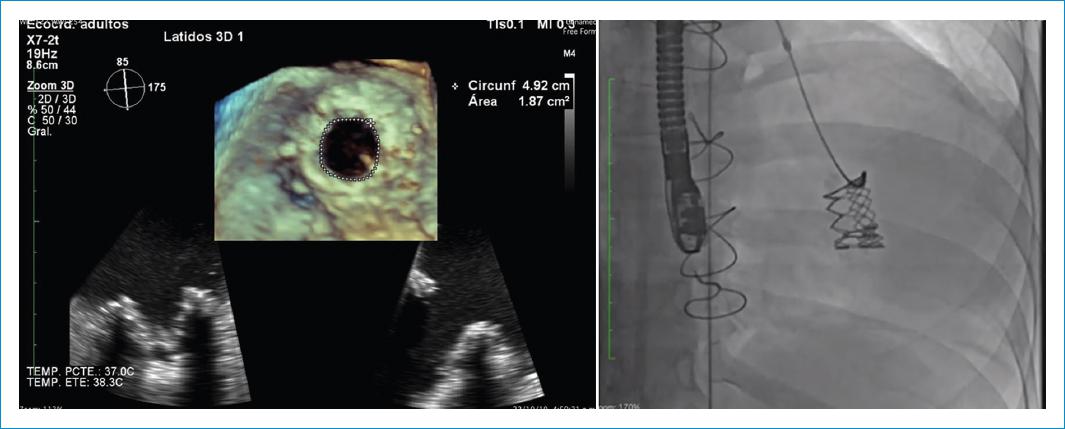

As soon as the patient was stabilized, with ventricular rhythm controlled, the valve in valve procedure was performed through right femoral vein, the kissing balloon technique was used with two 14 × 20 mm ultra-non-compliant balloons under pacemaker arrest (Fig. 2) and transesophageal echocardiographic monitoring, successful rupture of the biological prosthesis ring was achieved, which allowed the successful placement of the Edwards XT # 26 implant, with a residual peak gradient of 3 mmHg and mean 1 mmHg without valvular or paravalvular insufficiency evaluated with echo-TE intraprocedural monitoring (Fig. 3).

Figure 3 Final result: echocardiography and angiography image of percutaneous implant with new effective area of 1.87cm2.